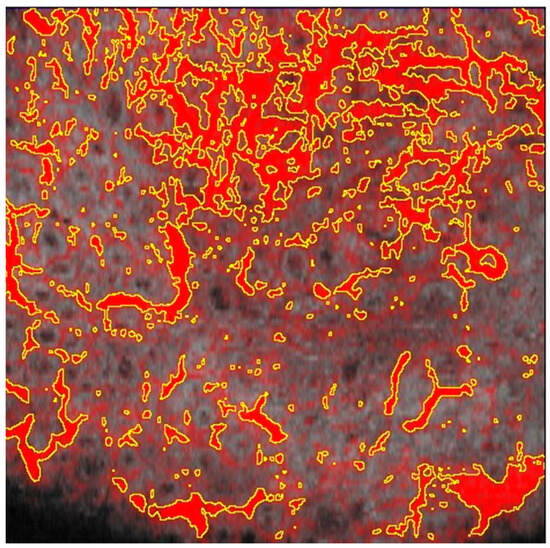

Figure 4.

D-OCT imaging at a depth of 300 microns. (a) pre laser treatment; (b) post laser treatment.

D-OCT imaging at a depth of 300 microns (Figure 4) offers a detailed visualization of the vascular and sebaceous structures in rhinophyma. Figure 4a, captured before treatment, displays a mesh pattern of blood vessels, characteristic of the condition’s vascular component. Additionally, gray structures visible in the image represent the sebaceous component of rhinophyma. Figure 4b, post-dye laser treatment, shows a significant reduction in the vascular mesh pattern, transitioning to an irregular and diffused pattern, indicating a decrease in the vascular component.